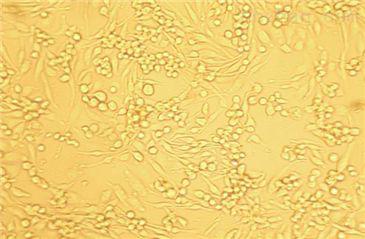

大鼠冠状动脉平滑肌细胞(原代细胞)

价格:

4860

品牌:

上海雅吉生物